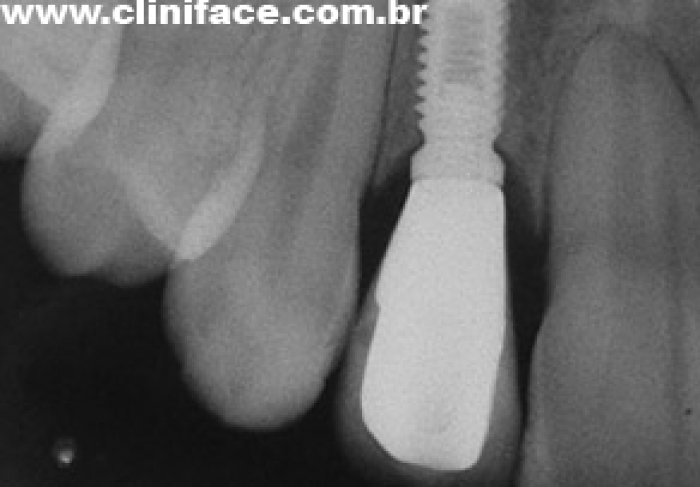

Imagens de implantes em incisivo lateral direito e esquerdo instalados

Imagem das próteses instaladas sobre os implantes